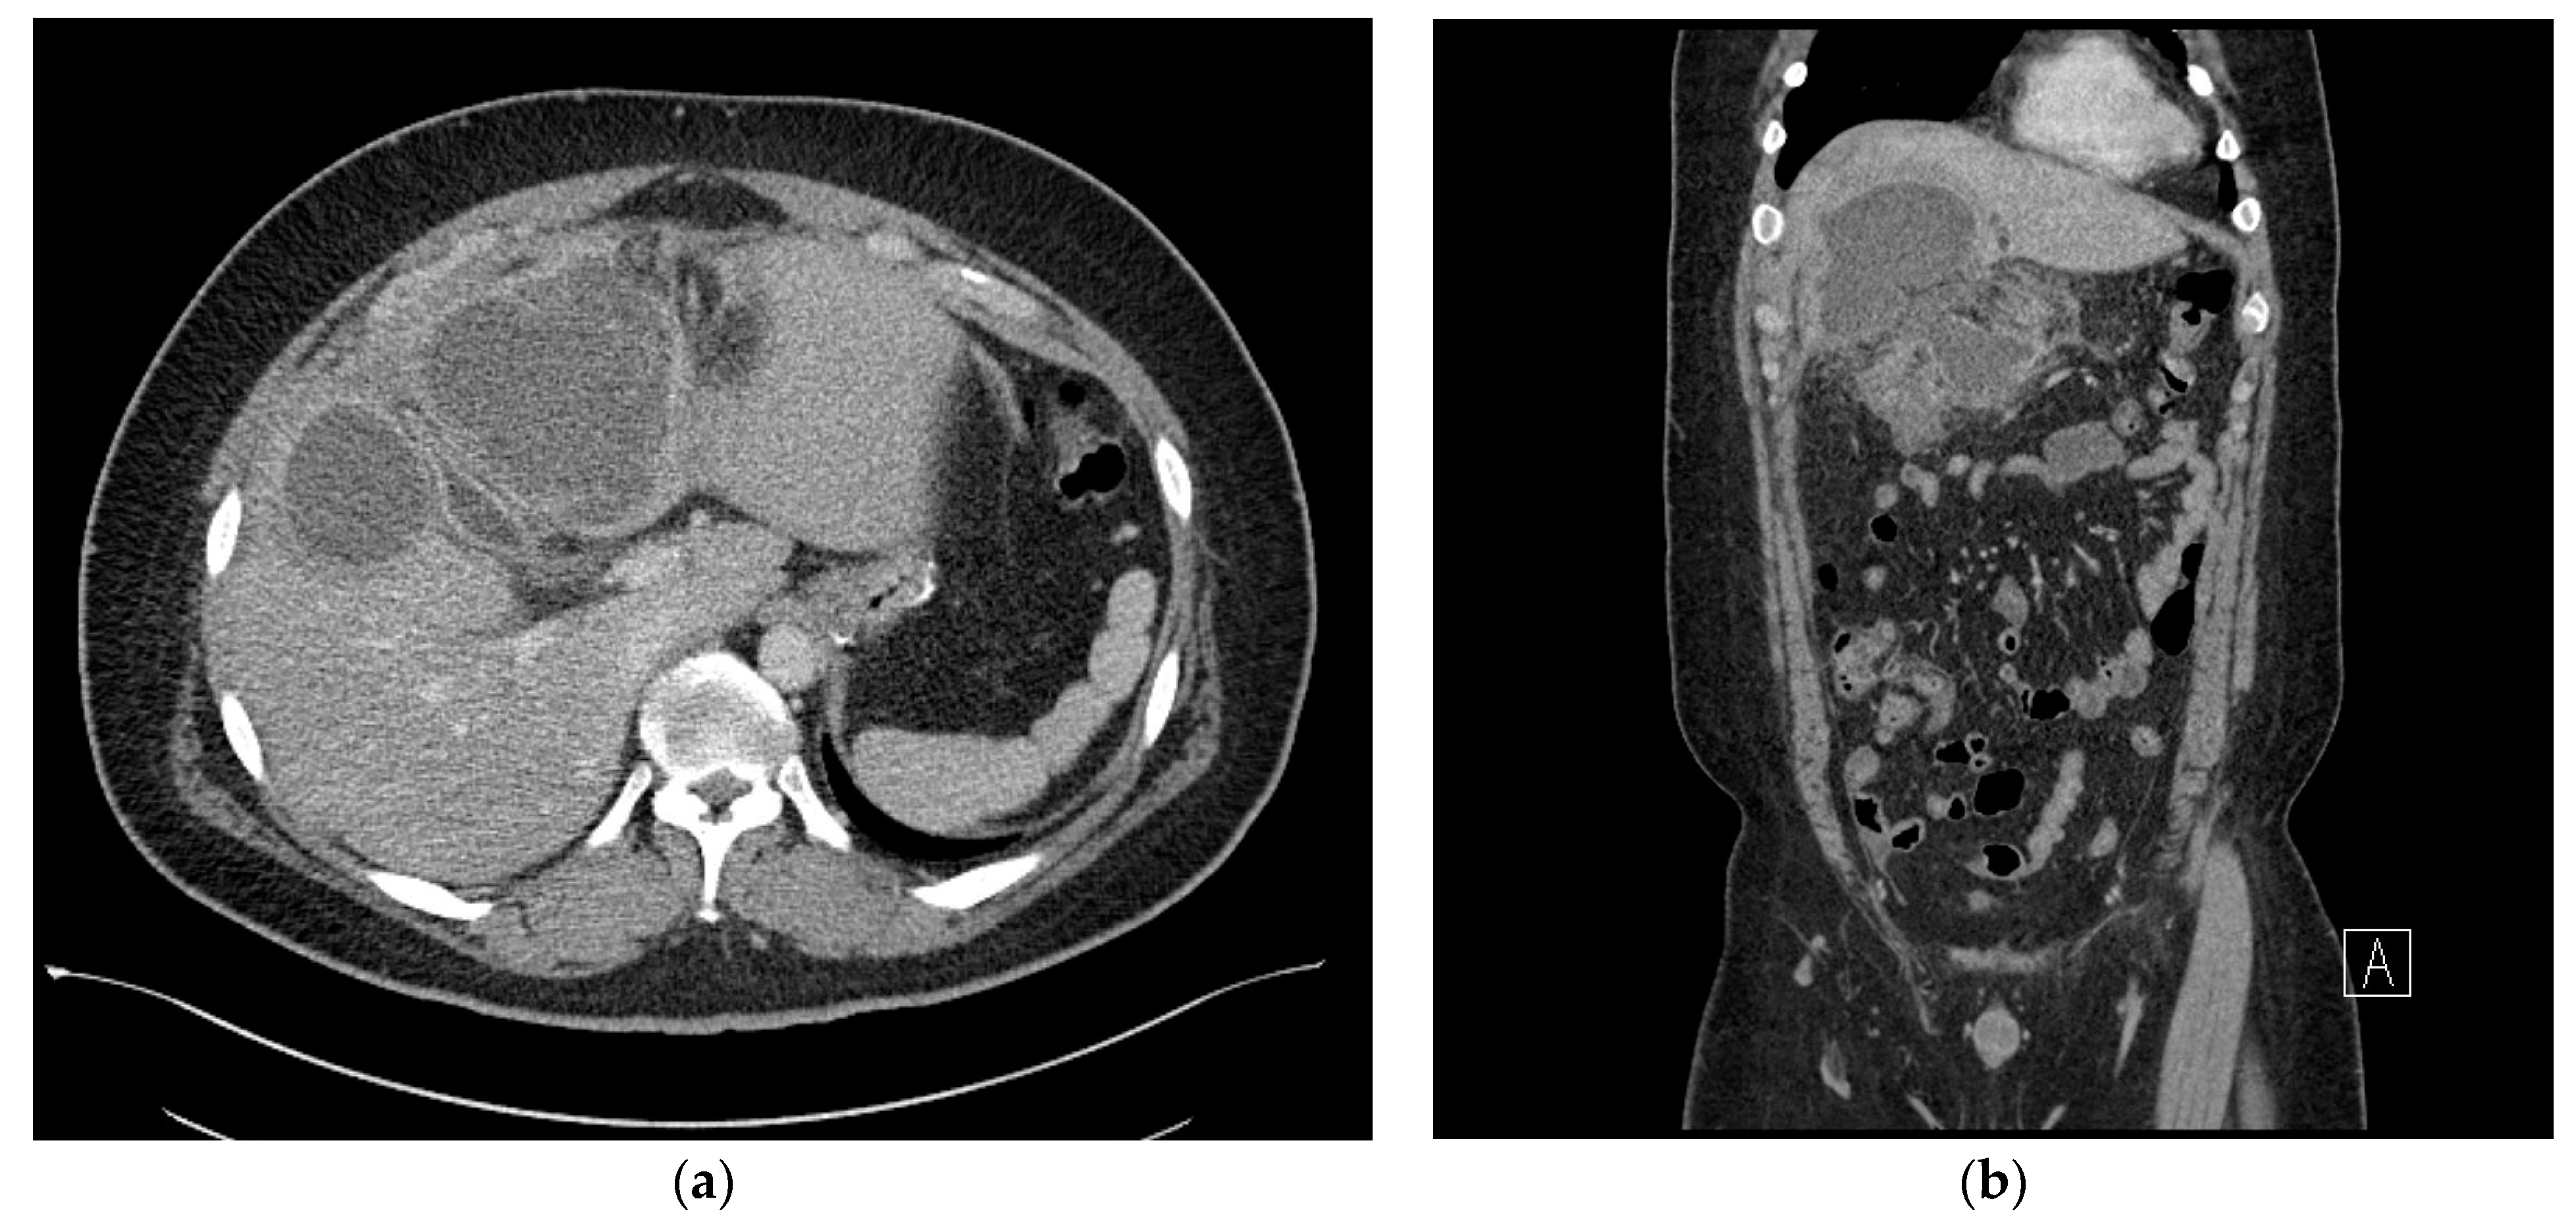

2. Case Presentation